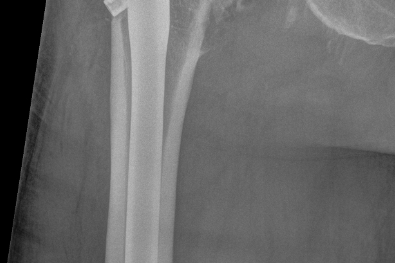

Hoftebrudd er en felles betegnelse for alle brudd i øvre del av lårbeinet. Hoftebruddene deles vanligvis inn i lårhalsbrudd, trokantære brudd og subtrokantære brudd (figur 1).

Lårhalsbrudd utgjør omtrent 60 % av hoftebruddene. Trokantære brudd utgjør omtrent ca 30 % av hoftebruddene og oppstår i området mellom den store lårbeinsknuten (trokanter major) og den lille lårbeinsknuten (trokanter minor) like nedenfor lårhalsen. Subtrokantære brudd utgjør omtrent 5 % av alle hoftebrudd og oppstår i området nedenfor den lille lårbeinsknuten (trokanter minor), altså lenger nede på lårbeinet enn de pertrokantære bruddene. Alle hoftebrudd må opereres. Bruddene legger derfor beslag på store ressurser i helsevesenet, både når det gjelder operasjonsstuer, sengeposter og opptreningsplasser.

Lårhalsbrudd

Lårhalsbrudd opereres på 2 ulike måter. Dersom bruddet står i pen stilling (lite forskutt) er det vanlig å operere bruddet med 2 pinner eller skruer (figur 2).